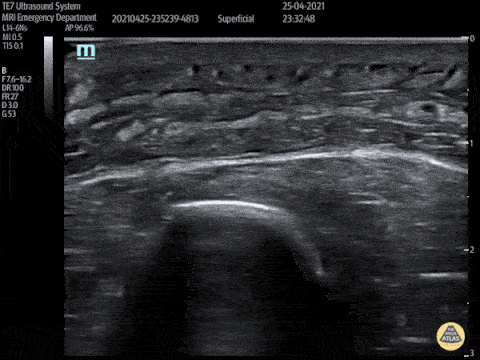

Soft Tissue - Post Stab Wound Cellulitis

This video shows a young man who presented 3 days after being stabbed to the arm. His wound had been sutured at the time but he had represented with erythema, pain and swelling to his forearm. POCUS showed cobblestoning consisent with cellulitis and excluded abscess and a foreign body. Peter Hulme Twitter: @Dr_Pete_EmMed